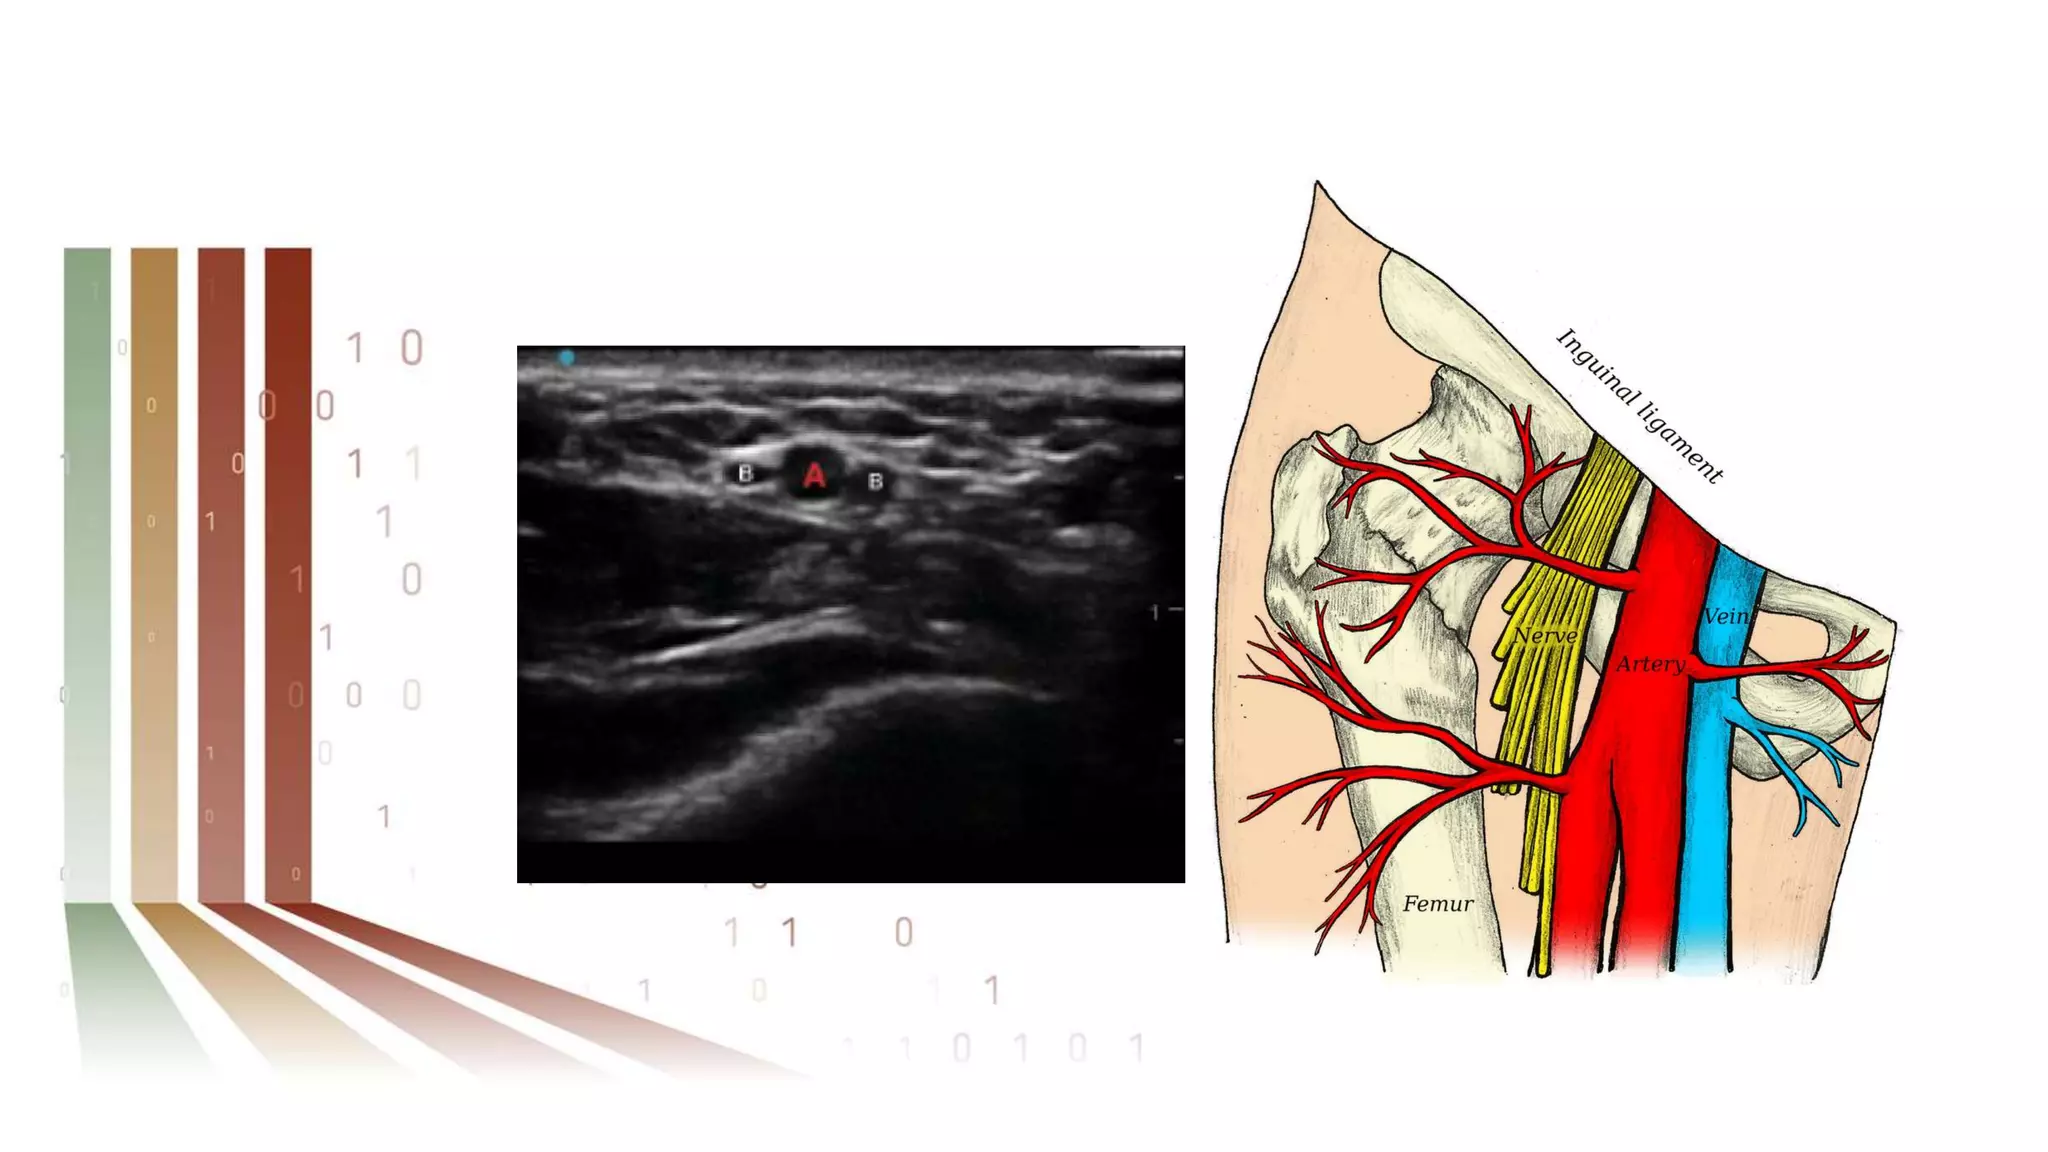

TRA should be achieved using

sonographic guidance with a

single-wall puncture technique

and the Seldinger technique with

a 21-gauge echogenic-tip needle.

Ultrasound reduces time and number of attempts to

achieve arterial access.

Use of ultrasound imaging may be helpful in

identifying an occluded RA that fills via retrograde

collaterals.

In addition, the use of ultrasound imaging that is

inclusive of the antecubital fossa may help reduce

crossover rates through the identification of radial

loops and other vascular anomalies.